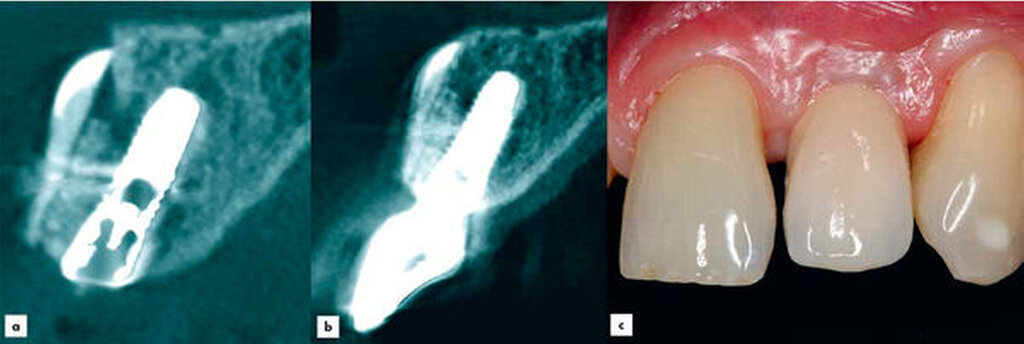

Die zuvor gewonnene und aufbereitete Dentinscheibe wurde mit Osteosyntheseschrauben (microscrews, Stoma, Emmingen-Liptingen, Deutschland) lateral des Defekts fixiert und das aufbereitete Dentinpartikulat in den Hohlraum zwischen Zahnscheibe und Implantat eingebracht (Abbildung 3d). Der Wundverschluss erfolgte spannungsfrei mit nichtresorbierbarem Nahtmaterial (Supramid 5/0, Serag-Wiessner, Naila, Deutschland). Postoperativ wurde ein DVT als Röntgenkontrolle angefertigt. Dieses zeigt das Implantat regio 22 in der Sagittalebene. Deutlich erkennbar ist die fixierte Zahnscheibe (Abbildung 4a).

Ein Jahr nach Implantatinsertion erfolgte eine radiologische und klinische Nachkontrolle. Aufgrund der Neuartigkeit der Technik, unklarer Volumenstabilität und unbekannter Risiken wurde ein DVT angefertigt. In einem ausführlichen Gespräch wurde dies mit dem Patienten erörtert. Der Patient entschied sich deshalb für die Anfertigung eines DVTs. Das im Rahmen der Nachkontrolle angefertigte DVT zeigte eine stabile vestibuläre Lamelle ohne erkennbare Resorption (Abbildung 4b). Das augmentierte Material erscheint sehr dimensionsstabil. Das Implantat sowie das periimplantäre Gewebe waren unauffällig (Abbildung 4c).